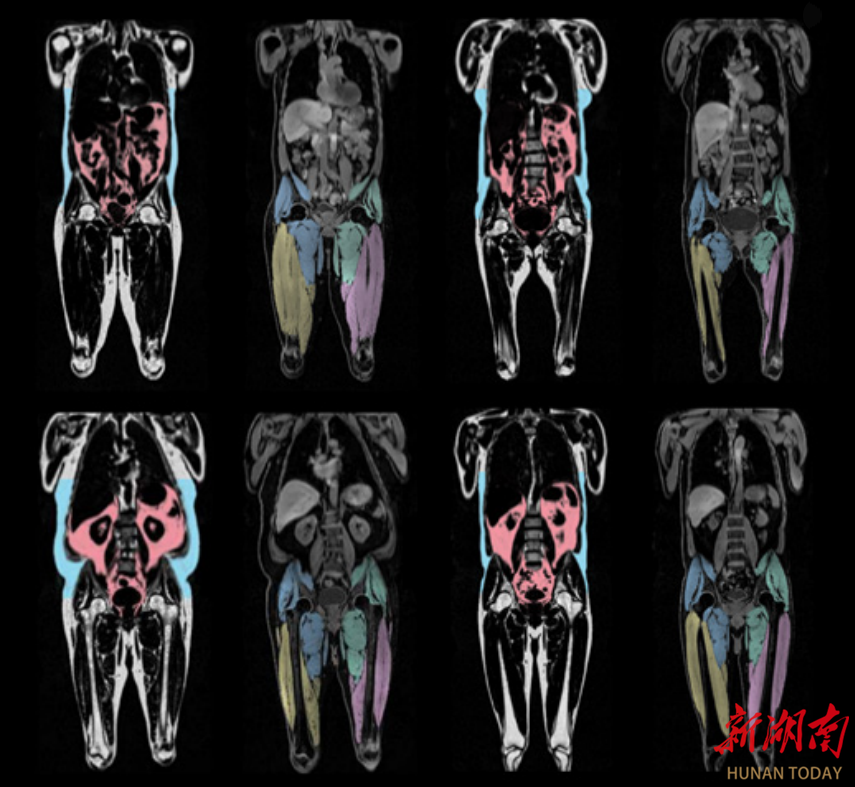

2025年8月,《欧洲心脏杂志》(EHJ)上发表的一项研究发现:内脏脂肪累积与男女心血管衰老加速相关,想要心血管衰老慢一点:一个部位要“细”——腰要细,两个地方要“粗”——臀围粗、大腿粗。

研究发现:腹部脂肪累积,会加速男性心血管衰老;腿部和臀部脂肪累积,会减缓女性心血管衰老。

具体而言,内脏脂肪每增加1升,加速心血管衰老约0.66年,女性腿部和臀部脂肪每增加1公斤,减缓心血管衰老约0.5年。